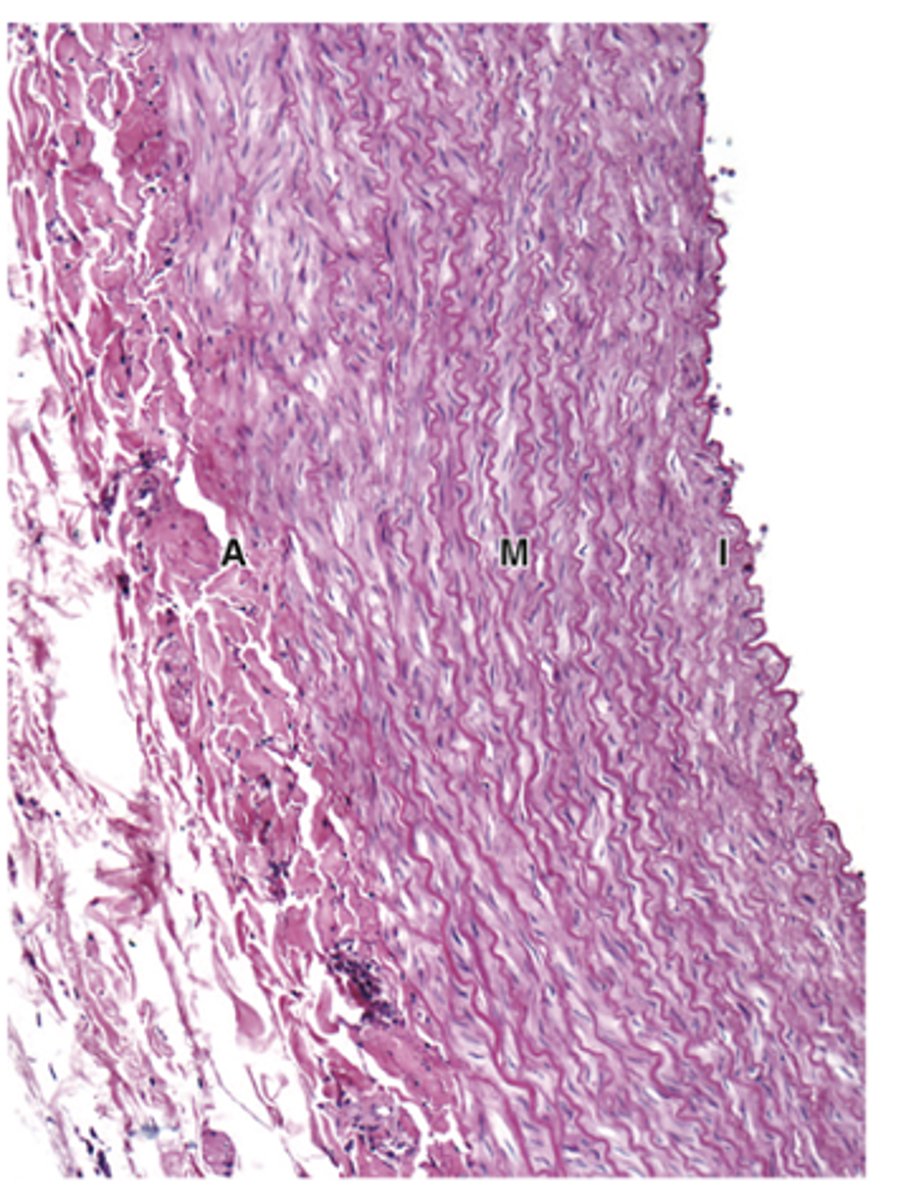

What is the composition of the tunica media and how does its thickness compare in arteries and veins?***

Smooth muscle and other varying components; thicker in arteries than in veins***

What is the composition of the tunica adventitia and how does its thickness compare in arteries and veins?***

Dense irregular connective tissue; thicker in veins than in arteries.***

In which vessels is the tunica media prominent with elastic lamellae?***

Only in arteries.

How does the tunica media in arteries compare to veins?

Thicker and contains much more elastin in arteries.

How is the tunica media of elastic arteries structured?

Thick, with fenestrated elastic lamellae alternating with layers of smooth muscle fibers.